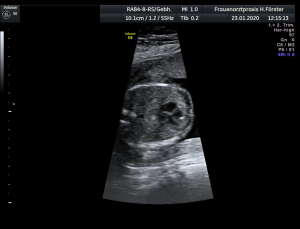

Gynäkologische Grundversorgung Frauenärztliche Krebsfrüherkennungsuntersuchung Nachsorge und supportive Therapie bei bösartigen gynäkologischen Tumoren Impfungen Brustultraschall Ultraschalluntersuchung der weiblichen Genitalorgane Psychosomatische Grundversorgung Chlamydienscreening FOB-Test (früher Hämoccult) Kontrazeption Geburtshilfliche Grundversorgung Geburtshilflicher Basisultraschall Erweiterter Basisultraschall (Organscreening) zw, 18-22.SSW Doppler/Duplexsonografie des fetomaternalen Gefäßsystems Infektionsscreening in der Schwangerschaft CTG (Kardiotokographie) Gynäkologische Grundversorgung Dies umfasst die Abklärung und Behandlung gynäkologischer Erkrankungen. Eine große Rolle dabei spielt das ärztliche Gespräch, ergänzt bei Notwendigkeit durch die gynäkologische Untersuchung oder Untersuchung der weiblichen Brust. In vielen Fällen werden noch Zusatzuntersuchungen durchgeführt (z.B. Ultraschalluntersuchungen, Abstrichentnahmen, Blutentnahmen) oder weiterführende Untersuchungen veranlasst (z.B. Röntgenuntersuchungen). >> zurück << Frauenärztliche Krebsfrüherkennungsuntersuchung Die Krebsfrüherkennungsuntersuchung der Frau ist wahrscheinlich die bekannteste Leistung unseres Fachgebietes. Ab dem Alter von 20Jahren hat jede Frau ein Anrecht auf diese jährliche Untersuchung. Dabei werden der Unterleib der Frau und ab dem Alter von 30Jahren auch die Brüste der Frau systematisch klinisch untersucht. Zusätzlich erfolgte seit vielen Jahren ein Pap-Abstrich vom Gebärmutterhals. So konnten Zellveränderungen meist rechtzeitig erkannt und behandelt werden und es wurde erreicht, daß das früher sehr häufige Zervixkarzinom (Gebärmutterhalskrebs) heute nur noch selten auftritt. Um die Qualität weiter zu verbessern erfolgte 2020 eine Neuordnung des Screenings mit Überarbeitung der Abstrichintervalle und Hinzunahme von HPV-Abstrichen ab 35 als Kassenleistung. >> zurück << Nachsorge und supportive Therapie bei bösartigen gynäkologischen Tumoren Nach Abschluss und oft auch wärend der Primärbehandlung können Probleme auftreten. Es macht also Sinn, sich in regelmäßigen Abständen zu treffen, um das weitere Vorgehen zu planen, eventuell Zusatzuntersuchungen zu veranlassen oder zusätzlich wegen der Beschwerden zu behandeln. Die Nachsorgeuntersuchungen finden anfangs engmaschig statt, später werden die Intervalle länger. >> zurück << Impfungen In Zeiten der Globalisierung, zunehmender Reisefreudigkeit und Zuwanderung werden wir wieder mit Infektionserregern konfrontiert, die wir schon als besiegt geglaubt hatten. Gleichzeitig werden wir immer älter und unser Immunsystem dabei nicht besser. Es reicht nicht, mal eben alle 10Jahre Tetanus zu impfen. Sind Sie geschützt? Wissen Sie was empfohlen ist? Bringen Sie den Impfausweis (auch den alten!!) mit. Wir prüfen Ihren Impfstatus, geben Ihnen Empfehlungen. Die gängigsten Impfstoffe haben wir auch vorrätig und können Sie impfen. >> zurück << Brustultraschall Die Ultraschalluntersuchung der Brust (Mammasonografie) kommt zur Abklärung von krankhaften Veränderungen zur Anwendung oder als Zusatzuntersuchung in der Früherkennung von Brustkrebs bei sehr dichtem Gewebe oder familiärer Vorbelastung. Sie ersetzt nicht das organisierte Mammographiescreening und ist nicht Bestandteil der normalen Krebsfrüherkennung. Es handelt sich um eine schmerzfreie Untersuchung ohne Strahlenbelastung. Die Mammasonografie  ist auch als Wunschleistung (IGeL) möglich. >> zurück << Ultraschalluntersuchung der weiblichen Genitalorgane Die Ultraschalluntersuchung der weiblichen Genitalorgane kommt zur Abklärung von krankhaften Veränderungen des weiblichen Genitales zur Anwendung. Dabei werden mit einer hochfrequenten Vaginalsonde die Organstrukturen im kleinen Becken untersucht. Die Untersuchung ist bei schlanken und sehr jungen Frauen auch vom Bauch aus möglich, die Genauigkeit ist dabei technisch bedingt aber schlechter.  Sie ist nicht Bestandteil der normalen Krebsfrüherkennung. Auch diese Untersuchung ist als Wunschleistung (IGeL) möglich. >> zurück << Psychosomatische Grundversorgung Jede Erkrankung belastet die Seele. Eine seelische Belastung macht den Körper krank. Jeder weiß das. Die Zusammenhänge zwischen dem kranken Körper und der kranken Seele beschreibt die Psychosomatik. Ein "Gordischer Knoten", der nur schwer zu zerschlagen ist, oft ein langer Weg. Ziel ist es, diese Zusammenhänge zu erkennen und den Betroffenen zu helfen ihren Weg zu finden. Oft ist die Zusammenarbeit mit einer Psychologin/ Psychologen nötig. Wichtig ist die Hilfe bei den ersten Schritten. Laufen müssen Sie selbst. >> zurück << Chlamydienscreening Das Bakterium Chlamydia trachomatis kann beim Sex übertragen werden und zu Entzündungen und sogar zur Unfruchtbarkeit führen. Deshalb bezahlen die Krankenkassen bis zum vollendeten 25.Lebensjahr allen sexuell aktiven Frauen einen Suchtest auf Chlamydien. Sie müssen lediglich eine Urinprobe abgeben. Auch in jeder Schwangerschaft wird nach Chlamydien gefahndet. Da Frauen im Normalfall auch im Alter über 25Jahren sexuell aktiv sind und noch schwanger werden wollen bieten wir die Testung auch als Wunschleistung (IGeL) an. Der Test wird dann aus einem Abstrich aus dem Muttermund entnommen, dies kann bei der Krebsfrüherkennung mit gemacht werden. >> zurück << FOB-Test (früher Hämoccult) Im Alter von 50 bis 54Jahren bezahlen die Krankenkassen allen versicherten Frauen einen Stuhltest zur Früherkennung von Darmkrebs oder seiner Vorstufen. Mit 55Jahren können Sie sich entscheiden zwischen zwei Darmspiegelungen im Abstand von 10Jahren oder der Fortführung der Stuhlteste alle 2Jahre. Natürlich kann man Stuhlteste auch zwischen den Darmspiegelungen machen lassen oder auch bei Frauen jünger als 50. Wir bieten dies als Wunschleistung (IGeL) unseren Patienten an. >> zurück << Kontrazeption Ein selbstbestimmtes Leben als Frau ist bei uns in Deutschland eine Selbstverständigkeit. Das war nicht immer so.  Kinder-Küche-Kirche hieß es früher, damals, in der guten alten Zeit. Das ist zum Glück vorbei. Und begonnen hat alles mit der Pille. Frauen konnten endlich über ihren Körper selbst bestimmen, ohne Angst ihre Liebe leben.  Aber die Pille ist nicht alles. Viele Märchen sind im Umlauf, Fehlinformation. Aber auch fehlendes Wissen zu Risiken.  Wir beraten Sie gern. >> zurück << Geburtshilfliche Grundversorgung In der Schwangerenberatung werden die werdenden Muttis gemäß den geltenden Mutterschaftsrichtlinien vom Anfang der Schwangerschaft bis zur Abschlussuntersuchung (6-8 Wochen nach der Geburt) betreut. >> zurück << Geburtshilflicher Basisultraschall Nach Vorgabe der Mutterschaftsrichtlinie sind sind in der Schwangerschaft 3 Ultraschalluntersuchungen vorgesehen. Diese finden in der 8.-12. SWW, in der 18,- 22. SSW und in der 28.-32.SSW statt. Dabei werden der Zustand des Embryos/ Feten, des Fruchtwassers und der Plazenta beurteilt. >> zurück << Erweiterter Basisultraschall (Organscreening) zw. 18-22.SSW Bei der zweiten Ultraschalluntersuchung (zw.18.-22. SSW) erfolgt ein erweitertes Screening mit Beurteilung der Organstrukturen des Kindes. Diese Untersuchung ist Kassenleistung, kann aber bei Wunsch auch Abgewählt werden, dann wird nur der Basisultraschall durchgeführt. >> zurück << Doppler/Duplexsonografie des fetomaternalen Gefäßsystems Bei Aüffälligkeiten im Schwangerschaftsverlauf oder auch bei bestimmten Vorerkrankungen oder Erkrankungen in einer früheren Schwangerschaft kann es notwendig sein die Durchblutung des Mutterkuchens und der Gefäße des Kindes zu Untersuchen. Hier kommt das Dopplerverfahren als Erweiterung des normalen geburtshilflichen Ultraschalls zum Einsatz. Dies erlaubt eine schnelle Zustandsbeurteilung des Kindes pepaart mit einer zeitlich begrenzten Vorhersage über die weitere wahrscheinliche Entwicklung. Bei entsprechender Indikation ist diese Untersuchung als Kassenleistung abrechenbar. >> zurück << Infektionsscreening in der Schwangerschaft Die Suche nach Krankheitserregern im Krankheitsfall ist Kassenleistung. Routinemäßig prüfen wir Ihren Schutz vor Röteln und Windpocken , in jeder Schwangerschaft erfolgt ein Test auf Chlamydien. Zusätzlich empfehlen wir jeder Schwangeren einen Test auf eine Besiedelung mit Gruppe-B-Streptokokken vor der Geburt. Diese Streptokokken können zu schweren Atemwegsinfektionen des Neugeborenen führen. Eine vorbeugende Behandlung bei positivem Test kann dann unter der Geburt erfolgen. Bei Wunsch kann auch ein erweitertes Erregerscreening über unser Labor erfolgen (Wunschleistung). Eine wichtige Rolle spielt auch die Kontrolle auf einen Schutz gegen eine Toxoplasmoseinfektion. Bei fehlendem Schutz empfielt sich die regelmäßige Testung aus dem Blut auf eine frische Infektion. Auch dies ist eine Privatleistung, wird aber von den meisten Kassen erstattet. Eine nicht erkannte und somit nicht behandelte Erstinfektion in der Schwangerschaft kann zu schweren Schäden beim Kind führen. >> zurück << CTG Ab etwa der 30.Schwangerschaftswoche können wir bei Notwendigkeit im Ramen der Schwangerschaftsvorsorge die kindlichen Herztöne (Kardiographie) und simultan dazu die die Spannung der mütterlichen Bauchdecke (Wehenschreiber, Tokographie) graphisch darstellen. Das nennt man zusammen Kardiotokographie oder kurz einfach CTG. Die Auswertung des CTG‘s erfolgt nach dem Fisher-Score (Punkte-System) sowie nach qualitativen Kriterien und erlaubt uns eine gute Zustandsbeurteilung des Kindes in den späteren Schwangerschaftswochen. >> zurück <<